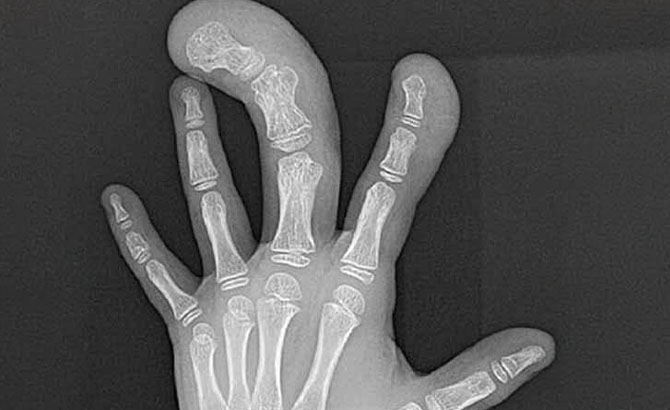

El dedo parecía haber sido cortado con precisión anatómica. La piel, de unos pocos milímetros de espesor, estaba rasgada en algunos puntos. Entre los pliegues secos Spörri distinguió que la uña estaba suelta y detectó restos de hongos. El hueso de la última falange, que sobresalía de aquella masa momificada, aparentaba ser leñoso.

El suizo se mostró escéptico y, por esa razón, Nagib le mostró varios documentos. Un certificado de autenticidad, papeles con caracteres árabes y latinos, así como una fotografía Polaroid del dedo y una radiografía realizada en los años 60.

Frank J. Rühli, experto suizo que analizó la momia de Ötzi, determinó que la fisiología, es decir, la falange proximal, la articulación media y la falange media, la falange distal y la falange distal, así como la uña y el lecho ungueal es idéntica a la de un humano pero desproporcionadamente grande. El dedo parecía auténtico, pero como los gigantes no existen (la ciencia sólo reconoce el gigantismo) creen que podría estar relacionado con macrodistrofia (o síndrome de Proteus). Esta condición implica el crecimiento excesivo de los dedos de las manos o de los pies del paciente.

También consultó al Dr. Benecke quien coincidió en el diagnóstico de una posible alteración de la macrodactilia. No obstante, el propio Spörri señala en su web varias razones por las que el dedo gigante de Bir Hooker no puede ser una macrodactilia:

1) Esta enfermedad se caracteriza principalmente por un agrandamiento patológico del tejido blando.

2) El crecimiento óseo se ve menos afectado. Si es así, suele manifestarse en un agrandamiento patológico de las partes óseas correspondientes.

3) En la reliquia, el hueso es anatómicamente correcto y coincide con las proporciones de la masa de tejido circundante.